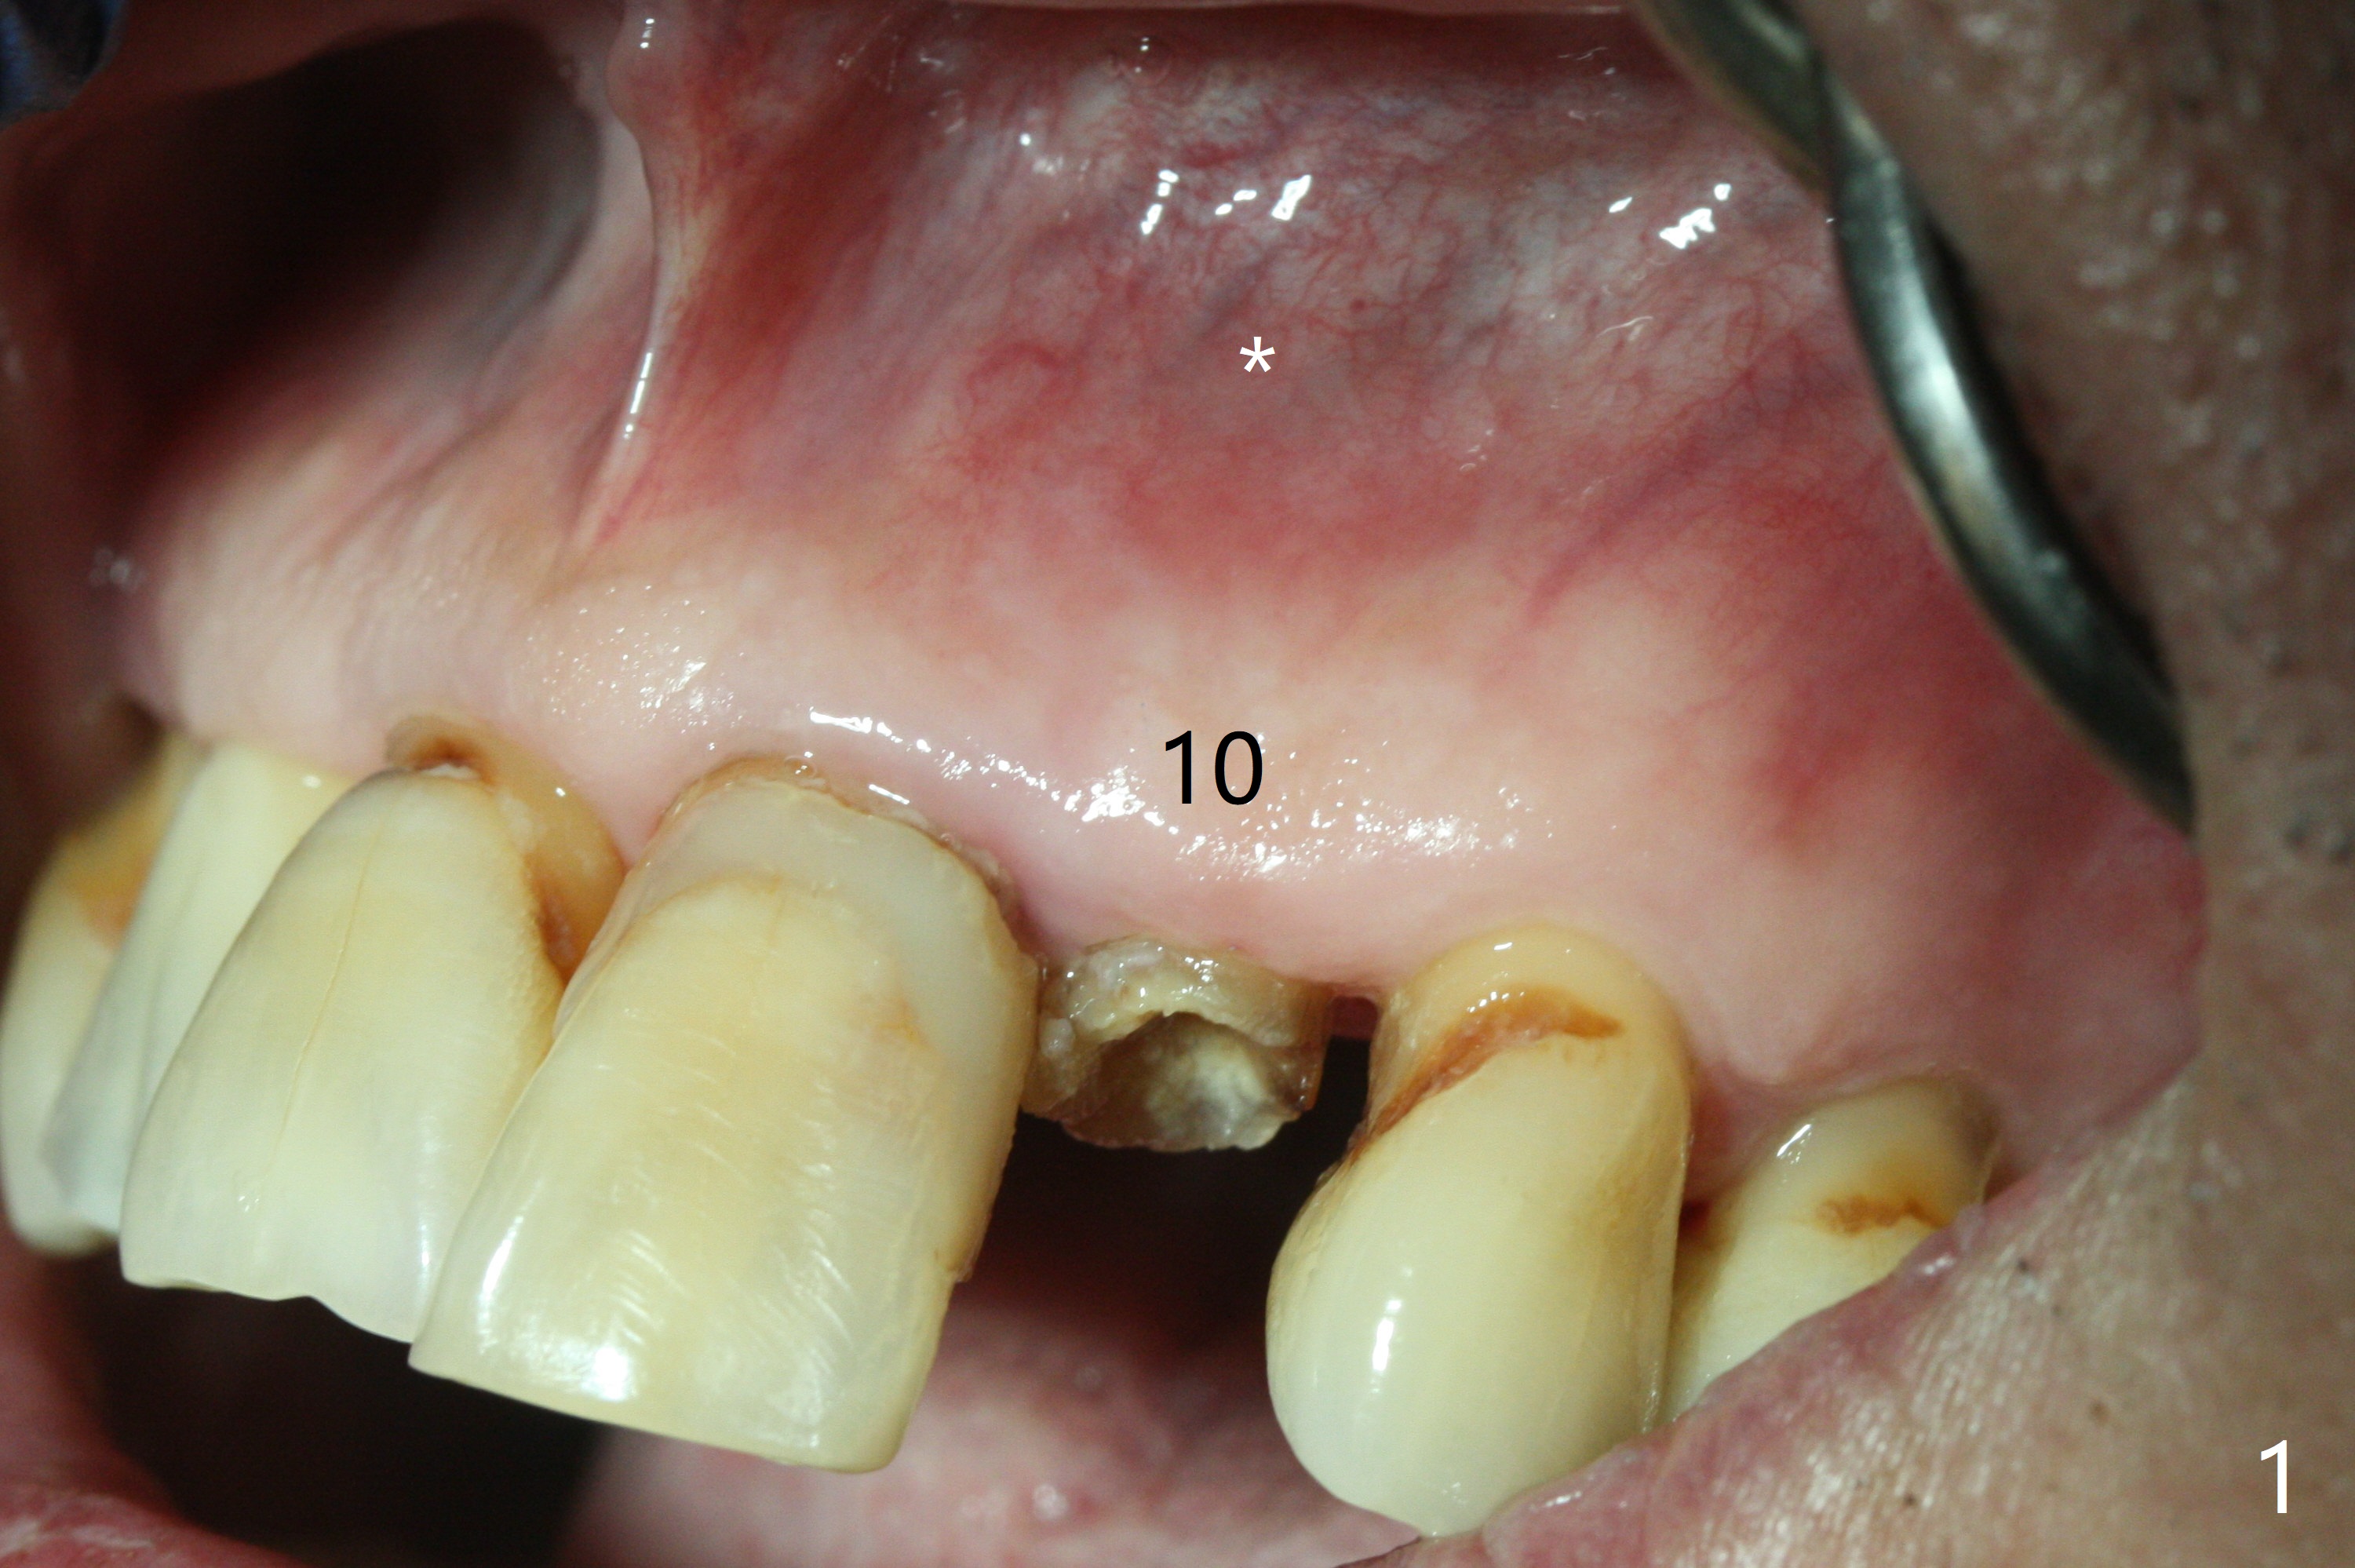

When the 67-year-old man returns for #23-26 crown/FPD cementation, the tooth #10 has fractured with necrotic pulp (Fig.1) and periapical radiolucency (Fig.2 (CT coronal section) *). He requests immediate implant since he has difficulty in getting ride from out of state. After curettage of the apical granulation tissue, a 3x16(2) mm 1-piece implant is placed with 20 Ncm because of slight overprep using 2 mm drill (Fig.3). Postop CT shows that the implant does not seem to be small (Fig.4). The fracture of the tooth #10 is related to edge-to-edge occlusion with the tooth #22 while the lower restoration is being fabricated in lab (Fig.5). It is easy to achieve occlusal clearance when the immediate provisional is fabricated with normal overjet. The density of the bone immediately next to the implant increases 6 months postop (Fig.6 *). The soft tissue also looks normal.